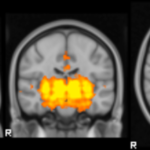

Un estudio dirigido por investigadores del Centro de Neurobiología del Aprendizaje y la Memoria de la Universidad de California en…